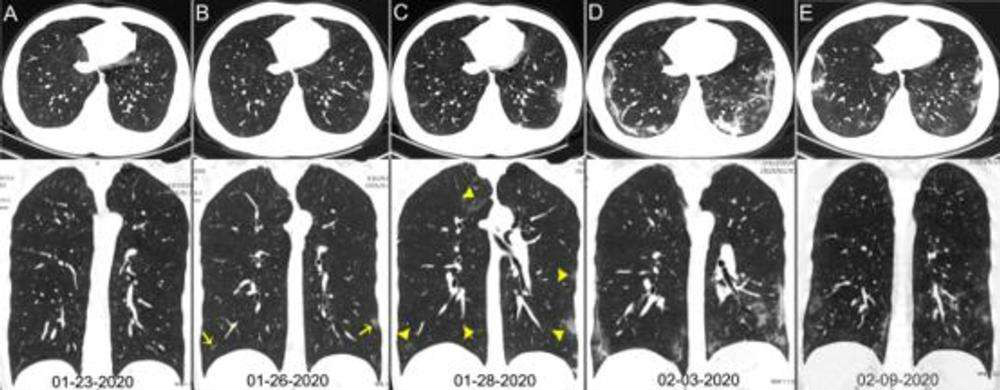

Através de radiografias pode ser mais difícil diagnosticar os danos no pulmão de um portador do covid-19. Porém, as tomografias mostram claramente os estragos feitos, como essas realizadas por uma equipe médica responsável pelo estudo que analisou pacientes de Wuhan, na China.

As imagens mostram claramente — para especialistas — a evolução da pneumonia. Por isso, os pesquisadores concluíram que o raio-x de tórax não é o exame ideal para diagnóstico da nova doença, mas sim a tomografia computadorizada. Esse último deve ser usado em caso de dúvidas na hora do diagnóstico correto do covid-19, se o médico achar necessário.